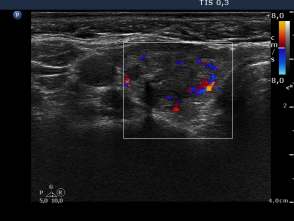

First session of the sclerotherapy (second row of images):

Clinical presentation: the patient had no complaints.

Hormonal investigation indicated subclinical hyperthyroidism (TSH 0.02 mIU/L, FT4 17.4 pM/L).

Ultrasonography: the nodule in the right lobe significantly increased.

Suggestion: definitive therapy. The patient chose ethanol sclerotherapy.

Five sessions of ethanol was administered. We gave 13 mL ethanol in all.